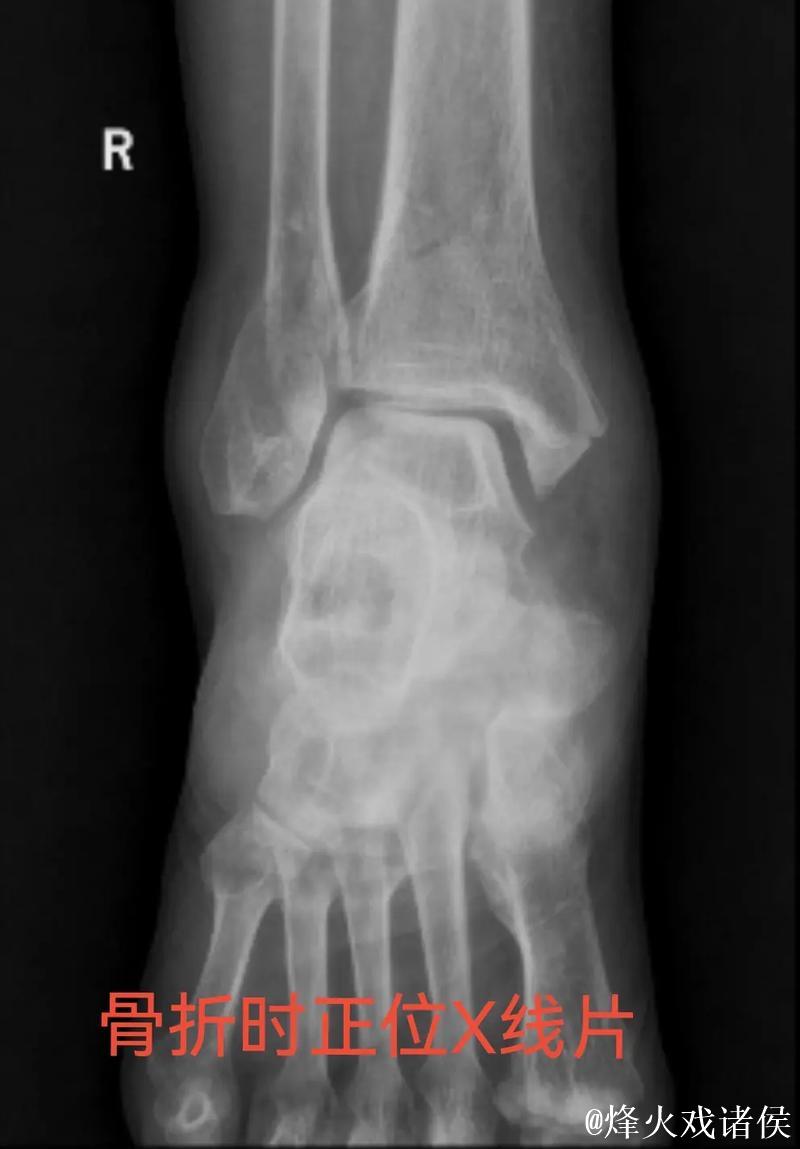

伤情解析 右踝三角韧带与腓骨骨折意味着什么

很多人在看到“右踝三角韧带断裂 右侧腓骨骨折”这样的医学表述时,只会感觉到“很严重”三个字,却未必真正理解其中的含义。踝关节三角韧带位于脚踝内侧,是一个由多条韧带组成的“组合体”,主要负责保持踝关节的内外稳定,防止小腿和足部出现异常翻转。当运动员在高速突破、急停、变向或落地时,如果脚踝遭遇过度外翻或扭转,三角韧带就可能被强行拉伸甚至撕裂。完全断裂不仅会造成剧烈疼痛,还会直接破坏踝关节的稳定性,使人几乎无法正常负重行走。与之同时出现的右侧腓骨骨折,大多与剧烈外力撞击或扭转应力有关。腓骨虽然不像胫骨那样承担大部分体重,但在踝关节的力学链条中起到重要支撑和协同作用。当韧带与骨骼在一次意外中同时受损,就意味着踝关节遭遇了极端应力,恢复与康复的难度成倍增加。

医学视角下的恢复周期 手术康复和不确定性

对于三角韧带断裂与腓骨骨折这种组合伤情,医学团队通常会综合评估踝关节稳定性、骨折位置与移位程度、软组织损伤范围,来决定是否采用手术治疗。若存在明显关节不稳或骨折移位,往往需要通过钢板、螺钉或钉棒内固定来重建骨性与韧带结构。在此之后,便是漫长而细致的康复周期。一般而言,骨折在数周内可以初步愈合,但韧带修复与功能恢复远比“骨头长好”更复杂。康复过程需要一套循序渐进的计划:早期的消肿与被动活动、中期的肌力与本体感觉训练、后期的专项运动模拟。每一个阶段若处理不当,都可能导致关节僵硬、力量不足或反复崴脚等后遗症。对职业运动员来说,问题不仅是“能不能走路”,而是“能不能继续高强度比赛、能不能保持原有水平”。任何轻微的落差,都可能在激烈竞争的职业舞台上被放大。